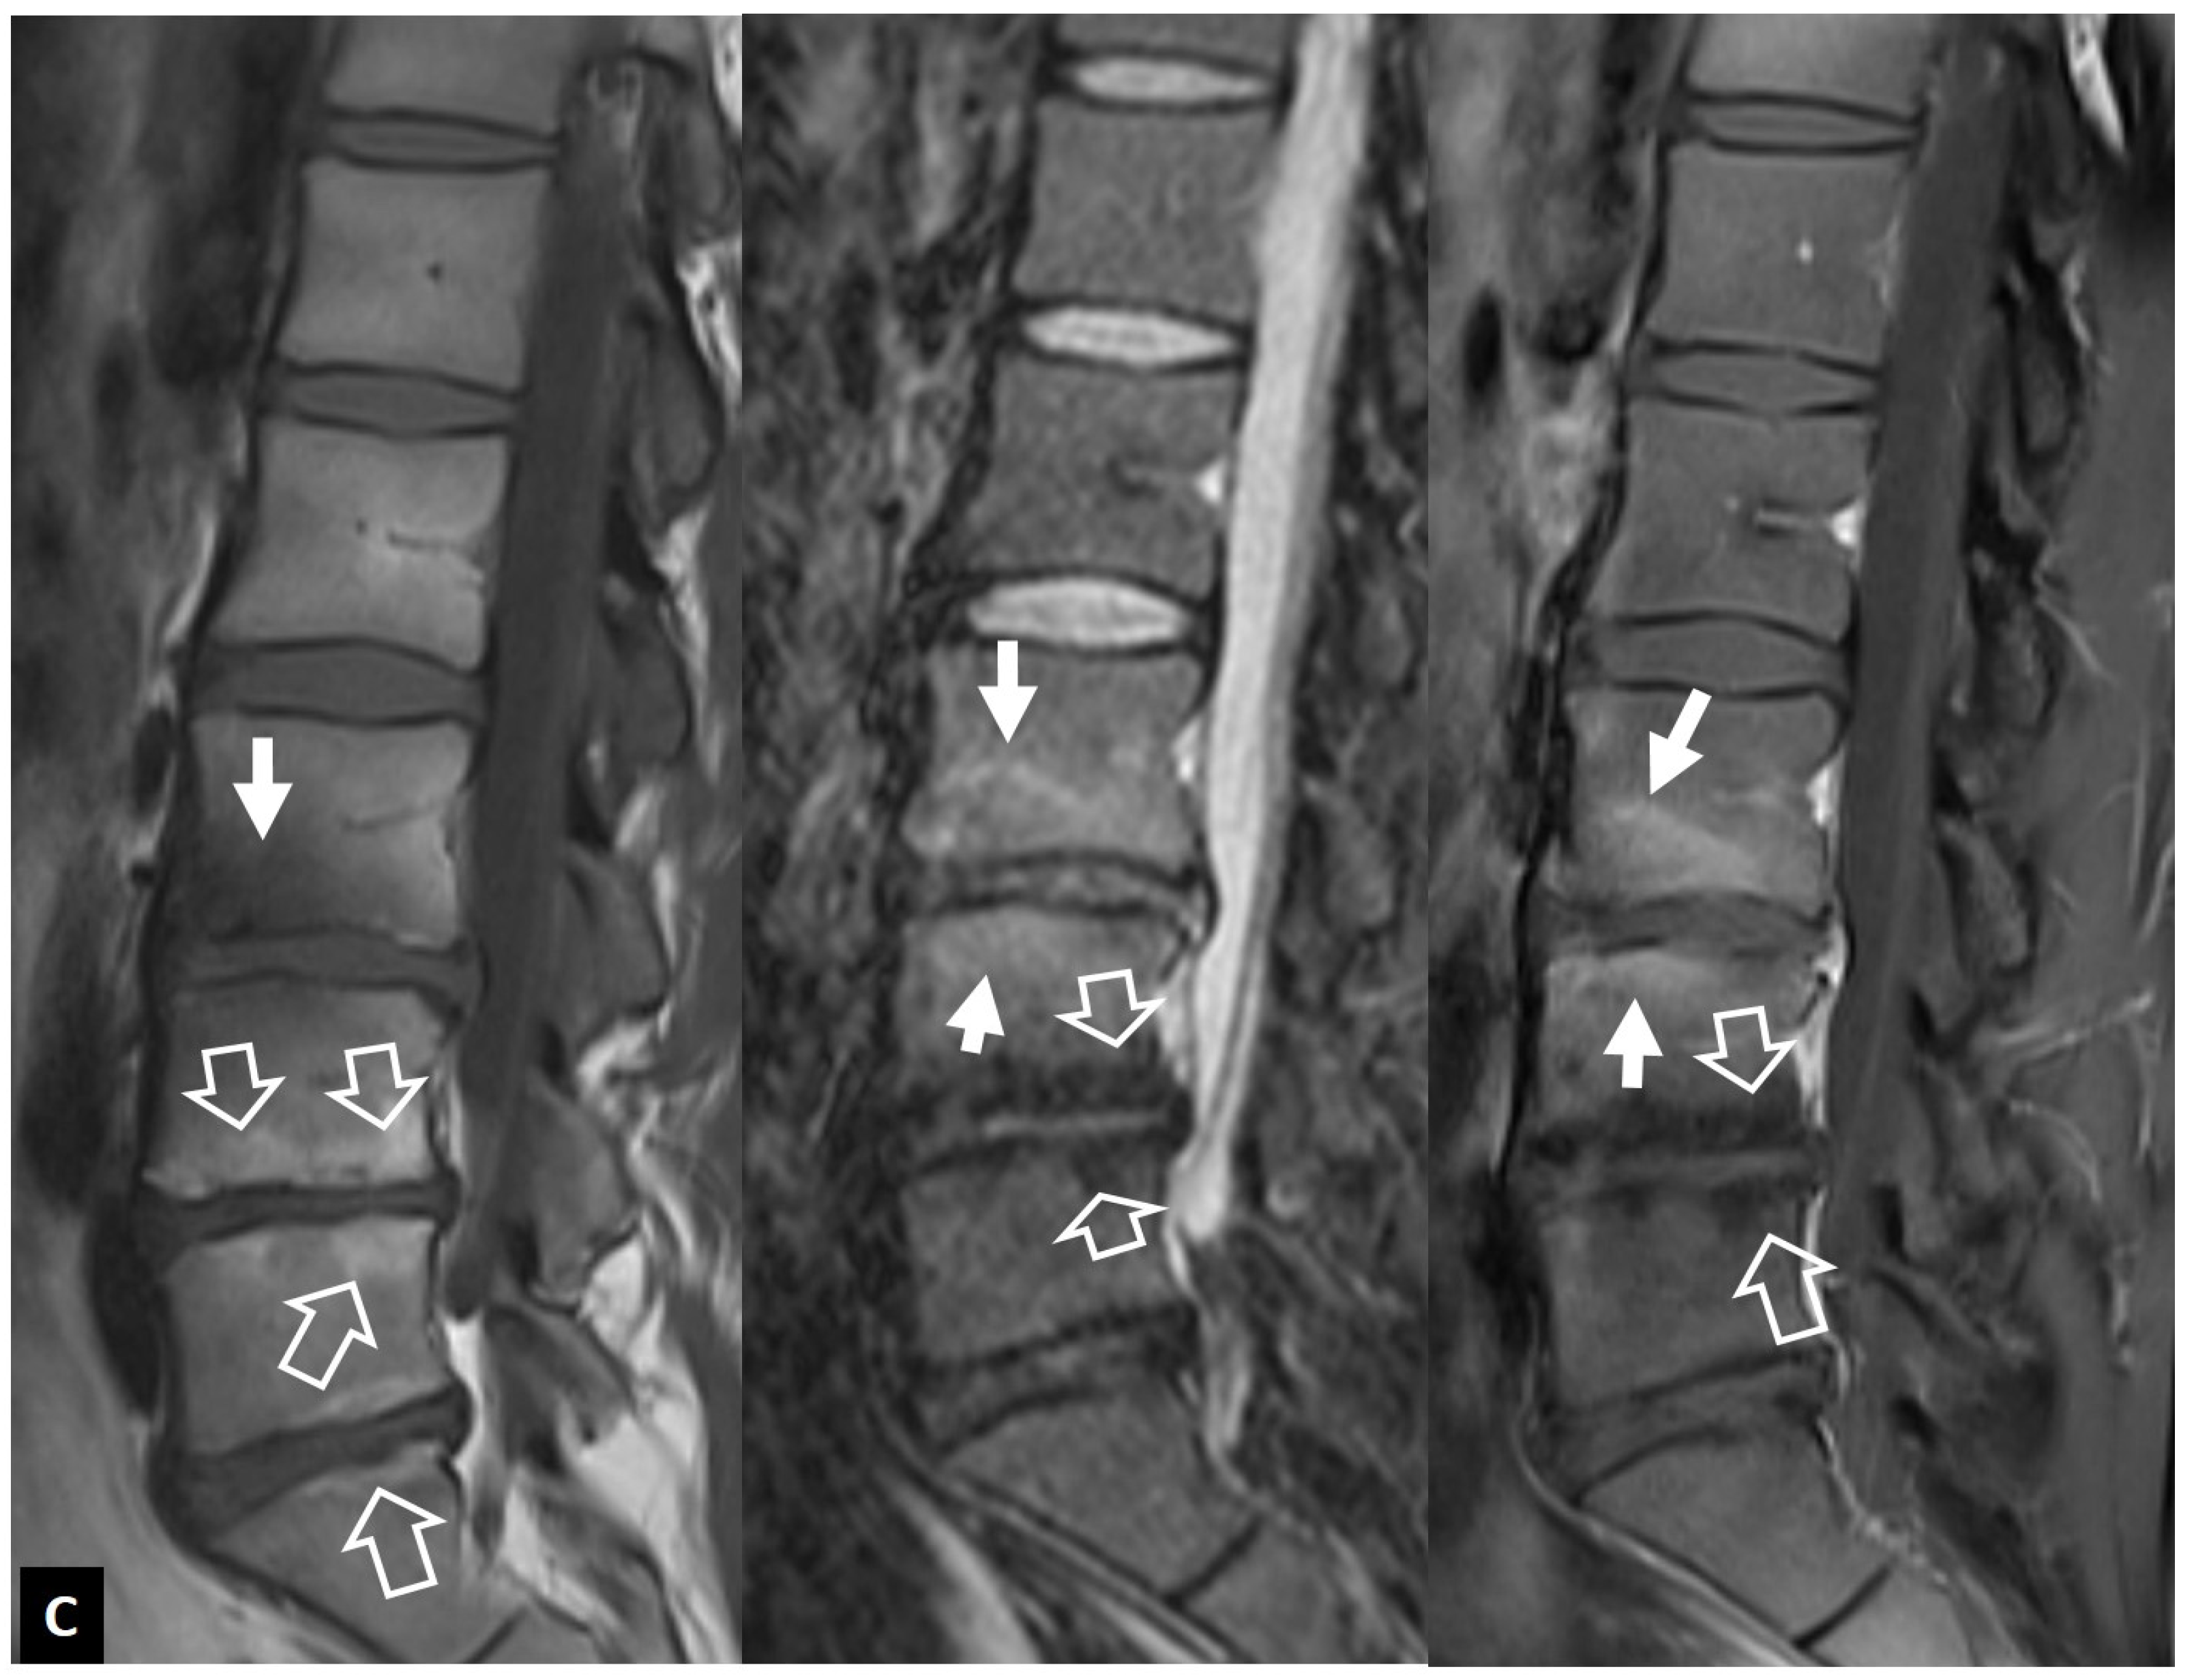

2.1.4. Destructive Spondyloarthropathy

2.1.5. Crystal Deposition

2.1.6. Post-Operative Aseptic Discitis